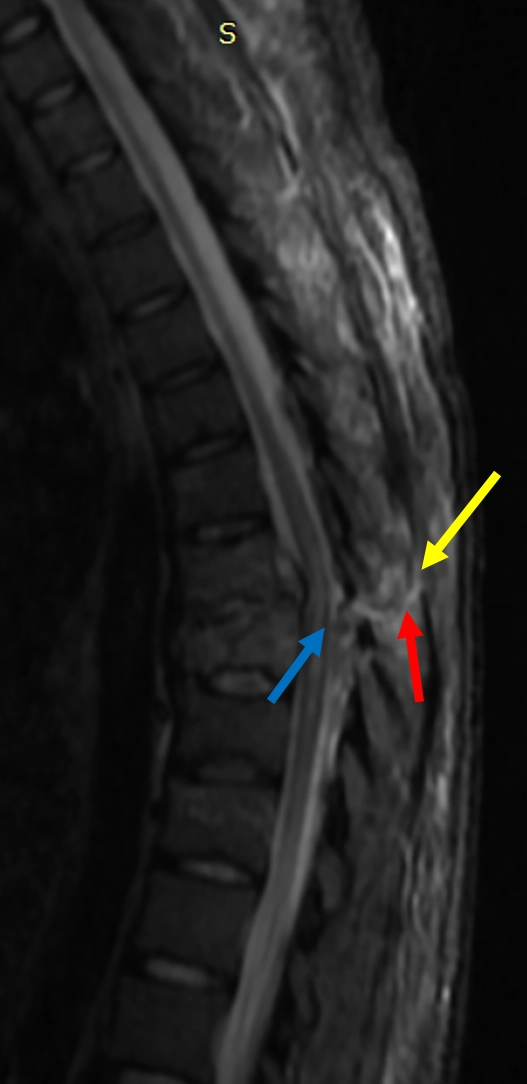

Tổn thương trượt xoay cột sống (Translation-rotation spine injuries)